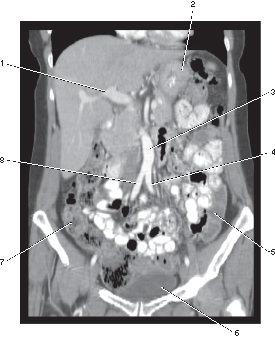

2

stomach